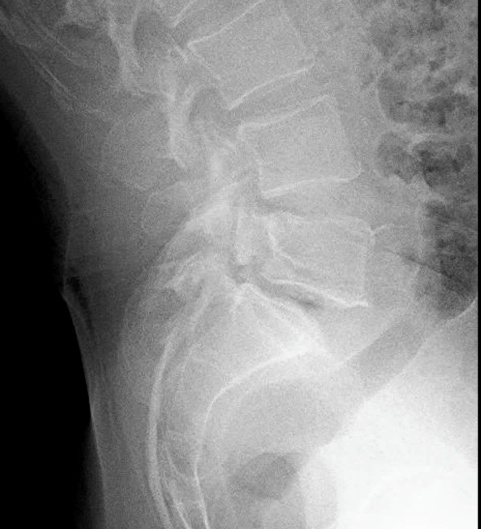

2.3. Điều trị bệnh lý cột sống: với sự hỗ trợ chuyên môn của Bệnh viện Chợ Rẫy, Bệnh viện Nhân Dân 115 TpHCM, Khoa đã và đang thực hiện phẫu thuật các trường hợp bệnh lý cột sống thắt lưng như: gãy cột sống; lấy nhân đệm thoát vị đơn thuần, qua kính vi phẫu; phẫu thuật trượt đốt sống; bơm xi-măng điều trị xẹp đốt sống do loãng xương;…Điều trị nội ngoại khoa các trường hợp Viêm thân sống đĩa đệm.

Phẫu thuật cột sống với sự hỗ trợ chuyên môn tuyến trên

Trước mổ

Sau mổ